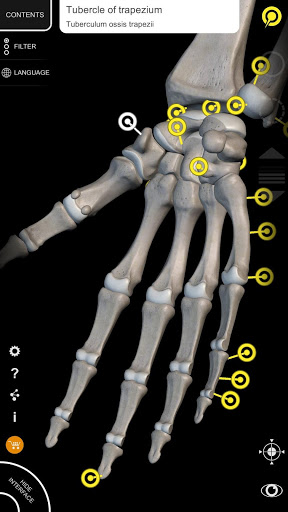

Завдяки простому та інтуїтивно зрозумілому інтерфейсу можна спостерігати кожну анатомічну структуру під будь-яким кутом.

Поділ за регіонами та попередньо визначені види полегшують спостереження та вивчення окремих частин або груп систем і зв’язків між різними органами.

• Функція пошуку, щоб легко знайти кожну анатомічну частину

• Вибравши модель або шпильку, з’явиться відповідний анатомічний термін

• Анатомічні терміни та інтерфейс користувача доступні 11 мовами: латинською, англійською, французькою, німецькою, італійською, португальською, турецькою, російською, іспанською, китайською, японською та корейською

• Анатомічні терміни можуть відображатися двома мовами одночасно.